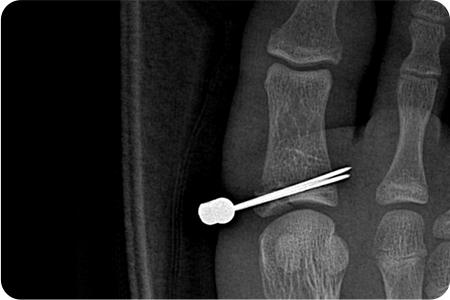

발가락 골절 수술

발가락 골절은 대부분 보존적 치료(깁스, 테이핑)로

회복되지만, 골절이 심하거나 뼈가 크게 어긋난 경우,

관절을 침범한 경우, 분쇄 골절에서는 수술이 필요

합니다.